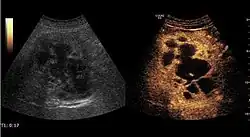

The ultrasound appearance is a well defined lesion, with very thin, almost unapparent walls, without circulatory signal at Doppler or CEUS investigation. The content is transonic suggesting fluid composition. The presence of membranes, abundant sediment or cysts inside is suggestive for parasitic, hydatid nature. Posterior from the lesion the acoustic enhancement phenomenon is seen, which strengthens the suspicion of fluid mass. They typically displace normal liver vessels but no vascular or biliary invasion occurs.

Liver cyst -

Hydatid liver cyst. Diagnostic criteria are the presence of membranes and sediment inside.